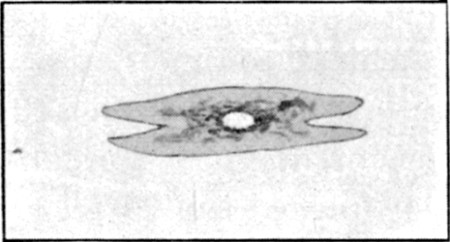

1. Section of Mauser Aperture of Entry To face p. 73

2. Section of Mauser Aperture of Exit 76

25a. Sections of Mauser Entry and Exit Wounds74